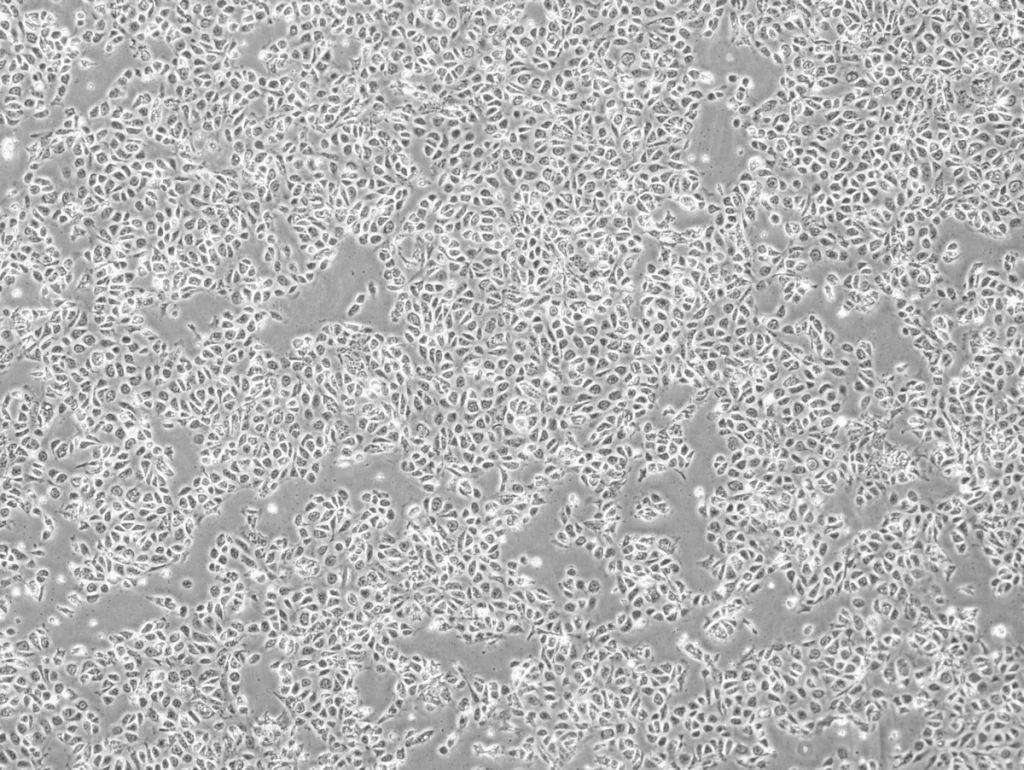

Karis Bio iPSC-Derived Endothelial Cells. Photo credit: Karis Bio

These iPSC-derived endothelial cells are then delivered back into ischemic tissues, where they trigger the formation of new blood vessels and restore circulation.